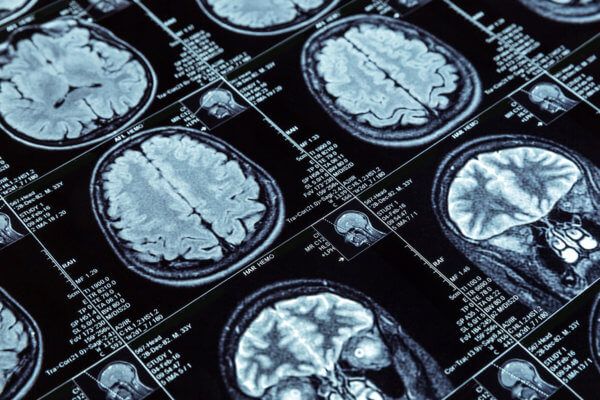

Peripheral neuropathy is a debilitating condition that affects millions of people worldwide. It occurs when the nerves that transmit signals between the brain, spinal cord,...